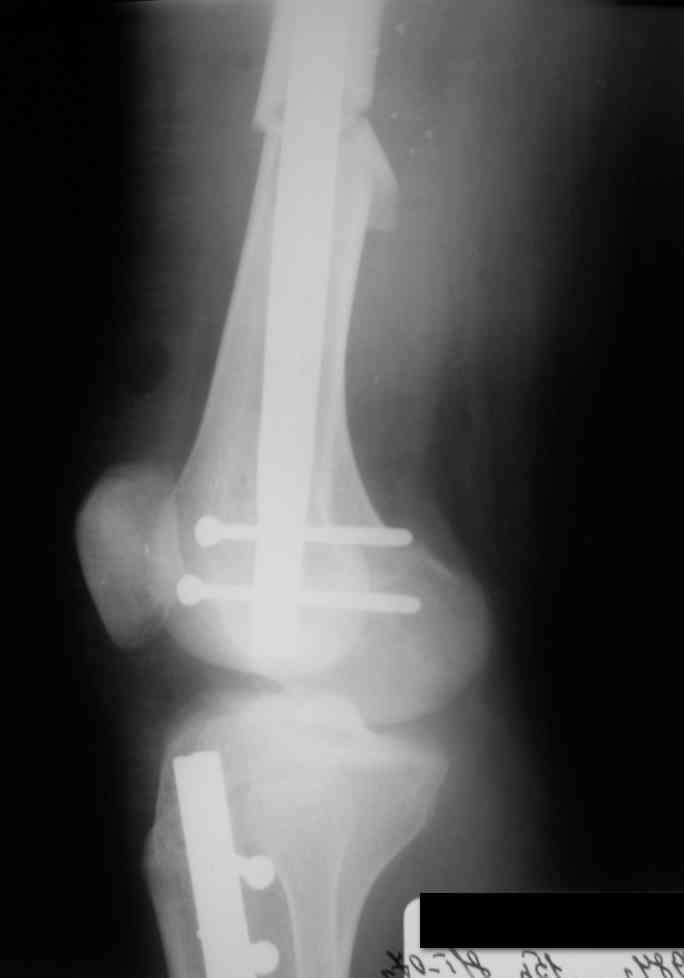

Дорогой Александр. Имею скромный опыт использования системы Fixion при переломах плеча, бедра и тибии. Всего 18 наблюдений с сентября 2006 г. Результаты отличные. Гвоздь индивидуален для каждого медуллярного канала. Легко имплантируется как в узкий, так и в деформированный канал. Это позволяет применять метод интрамедулярного остеосинтеза без ненужных потерь времени операции, флюороскопии и реально снижает крвопотерю и операционный риск. Удаление происходит без проблем. Особенно интересны больные с ипсилатеральными переломами бедра и голени.

В отношении ранней нагрузки при спиральных переломах лучше не торопиться. По данному случаю необходимо достигнуть исчезновения щели между штифтом и внутреним кортексом по Rg. А так картинка прекрасная - и длина сегмента и репозиция. Можно поздравить, коллега!

Да, спасибо за интересные иллюстрации. Получилось очень симпатично. На большеберцовой кости непременно надо было винты? Там же был торцовый упор, перелом в средней трети?

Это при раздувании гвоздя, или сейчас? Если второе, то я не понял. А так - давление повышали до 80 ата, перестали нагнетать, когда перестало снижаться меньше 70.

Спасибо, мы старались, чтобы первый блин не был комом.